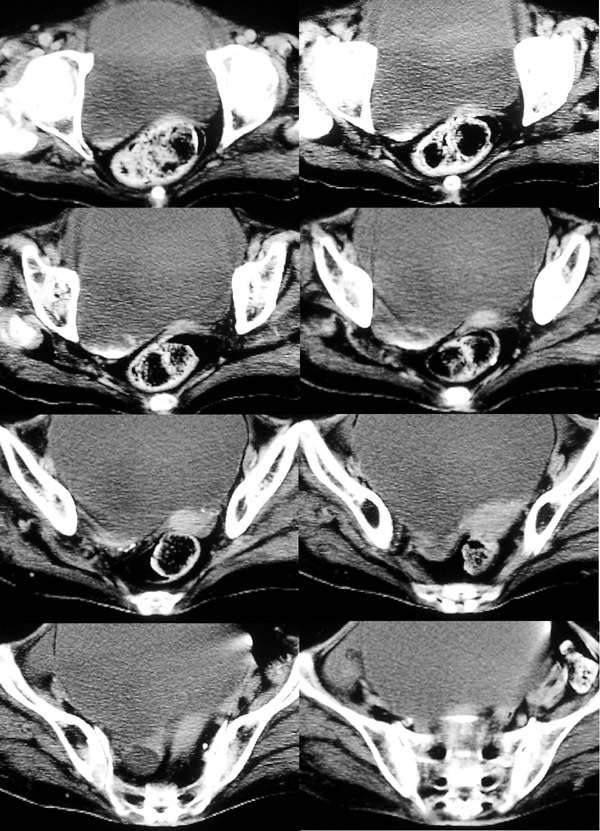

盆腔ct平扫

盆腔ct平扫,平扫ct

每日一例95667岁女盆腔包块半年ct平扫增强后什么结果

ct5699[原创[讨论]盆腔

ct腹部平扫 增强(一周后有病理)

盆腔ct图解

盆腔ct图片

盆腔CT

盆腔ct图片详解

女性盆腔CT